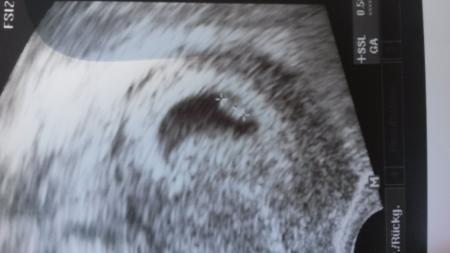

Hallo was erwartest du denn am Anfang der 6ssw zu sehen. Ne hohe schleimhaut vielleicht und je nach dem mit ganz ganz viel Glück ne Frucht hülle. Wobei man meine erst bei 5+6 also ende der 6ssw gesehen hat und dann war diese auch völlig leer. zwei Wochen später war dann alles so wie es sein soll. einfach abwarten und dem ganzen Zeit zum wachsen geben. Lg nita

Ich war in der 6.ssw beim Frauenarzt und ich hab dir mal mein Us -Bild mit dran gehangen. Das Herz schlug auch schon...

Bild zu